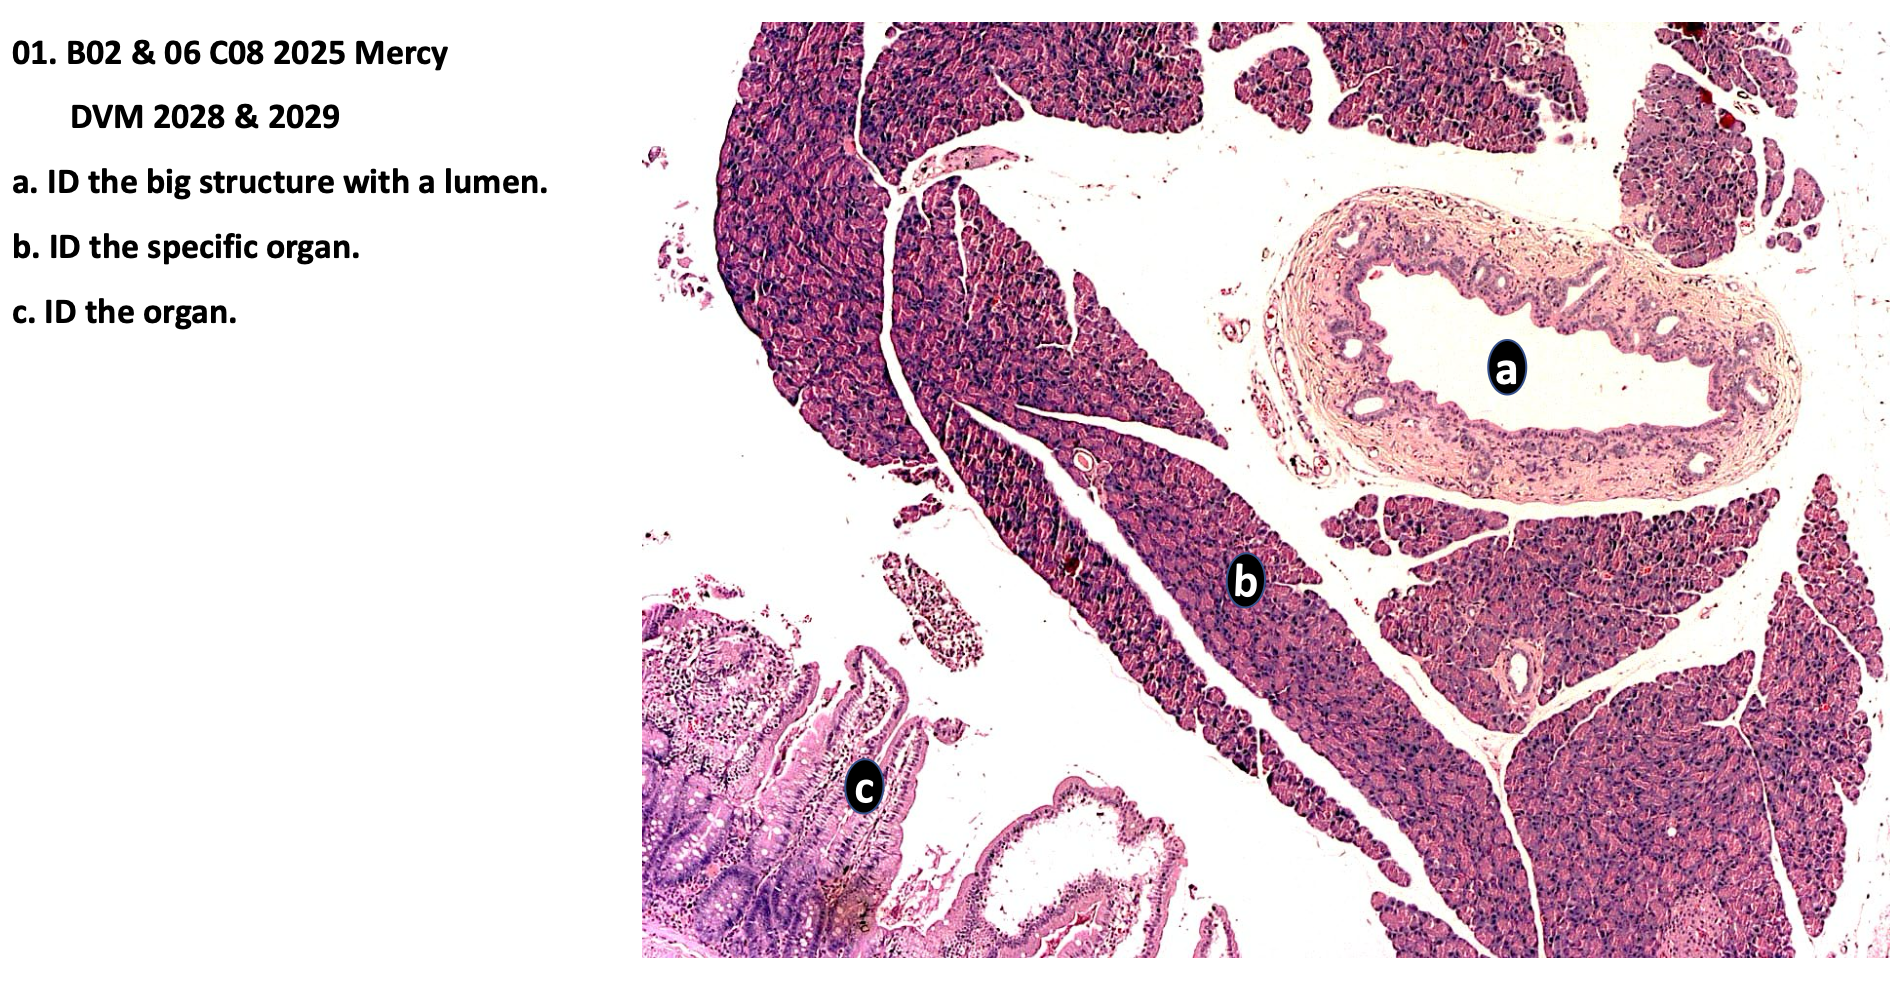

a. ID the big structure with a lumen

Main pancreatic duct

b. ID the specific organ

Pancreas

c. ID the organ

Duodenum